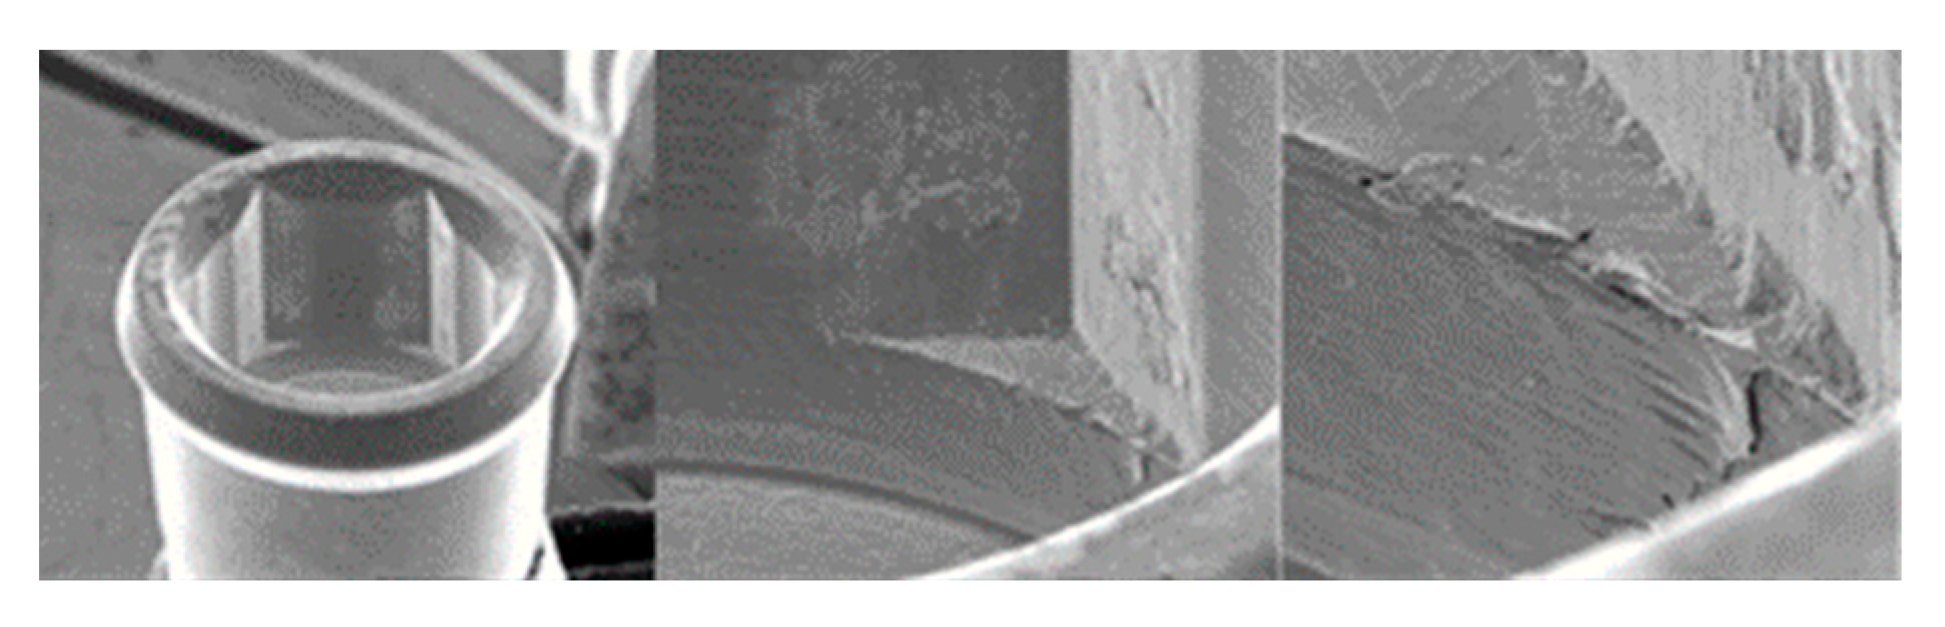

3.1.1. KL Implants

3.1.2. Essential Implants

3.1.3. SK2 Implants

3.1.4. Vega Implants

4.1. SEM Evaluation